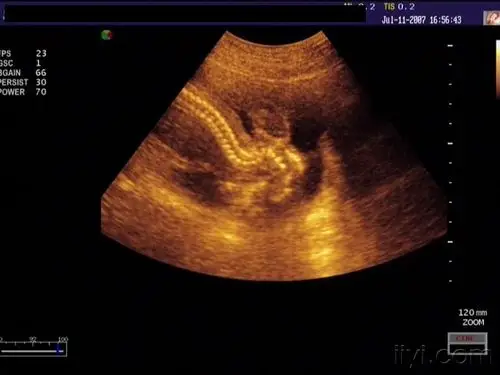

无脑儿 - 超声医学讨论版 - 爱爱医医学论坛

无脑儿:郭某 24岁 孕28周,早孕外院超声"无异常".